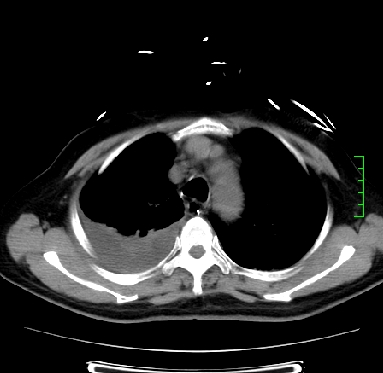

icu病人,几天都没明确诊断。m,76y,咳嗽、咳痰1周,伴气促,右胸痛入院,pe:t38.3c p135 r25 bp135/85。双肺可闻及大量湿罗音,心、腹未见明显异常。诊断:1心衰?2肺部感染?3冠心病?

11号ct

双肺感染性病变,下叶膨胀不全,胸水,左室大。

1)两肺感染性病变(右肺下叶肺脓肿可能)。2)双侧胸腔积液,以右侧为甚。

混合型肺水肿合并感染,肺膨胀不全,胸膜肥厚粘连包裹,同时肺内有陈旧性病灶。注意复查

考虑双肺感染、右肺下叶肺脓肿伴双侧胸腔积液。

ards,肺感染性病变,右下叶实变,双侧胸腔积液,右侧为著,叶间胸膜积液,右上肺陈旧性tb纤维灶,左室大。

考虑双肺感染、右肺下叶肺脓肿伴双侧胸腔积液,肺水肿。

考虑:双肺感染、右肺下叶肺脓肿,双侧胸腔积液,肺水肿.请结合临床.